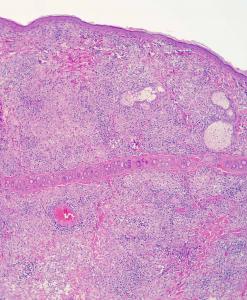

Leishmaniasis en hurón

Ésta es la primera descripción de leishmaniasis en un hurón, eficaz y diligentemente trabajada, como siempre, por Jacobo Giner de Centro Veterinario Menescalia, con la colaboración de la Universidad de Zaragoza y publicada en Veterinary Parasitology: Regional Studies and Reports 19:100369, 2020. doi: 10.1016/j.vprsr.2020.100369. Con esta publicación, Jacobo logró el 2º premio de los Premios de Divulgación Científica 2020 del Ilustre Colegio de Veterinarios de Valencia; aunque Jacobo está acostumbrado a ganar premios y seguro que tiene entre ceja y ceja el primer premio, nuestras más sinceras felicitaciones por este extraordinario logro y ánimos para que siga persiguiendo el primer premio y así pueda invitarme a esas cenas que me debe en el restaurante de cocina de autor Almoraduz, Puerto Escondido (Oaxaca). No se pierdan el taller de Medicina y Patología de Hurones del Congreso Solidario de Medicina y Conservación de Fauna Exótica y Salvaje de Puerto Escondido con Jacobo, Mike Garner y un servidor, va a ser extraordinariamente rico en medicina, patología y humor...cuando de una vez por todas podamos celebrar este congreso. ¡Bravo, Jacobo!.